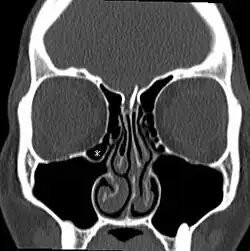

Haller-Zelle (Stern) in einer CT der Nasennebenhöhlen

Unter einer Hallerschen Zelle versteht man eine zusätzliche Siebbeinzelle (Ethmoidalzelle), die im Orbitaboden oder im Dach der Kieferhöhle zu finden ist. Sie wurde erstmals von Albrecht von Haller, einem Schweizer Anatomen, beschrieben. Es handelt sich hierbei um eine anatomische Normvariante, die je nach Literaturangabe bei 5 % bis 30 % der Bevölkerung zu finden ist. Hallersche Zellen werden meist als Zufallsbefund in einer computertomographischen Untersuchung des Gesichtsschädels gefunden.[1] Sie könnten bei ungünstiger Lage den Abfluss von Sekret aus der benachbarten Kieferhöhle behindern. Manche Studien sprechen für eine Assoziation größerer Haller-Zysten mit Nasennebenhöhlenentzündungen (Sinusitiden),[2][3] andere nicht.[4][5] In jedem Fall ist die Information über diese anatomische Variante zur Planung eines operativen Eingriffs wichtig, um Komplikationen zu vermeiden.